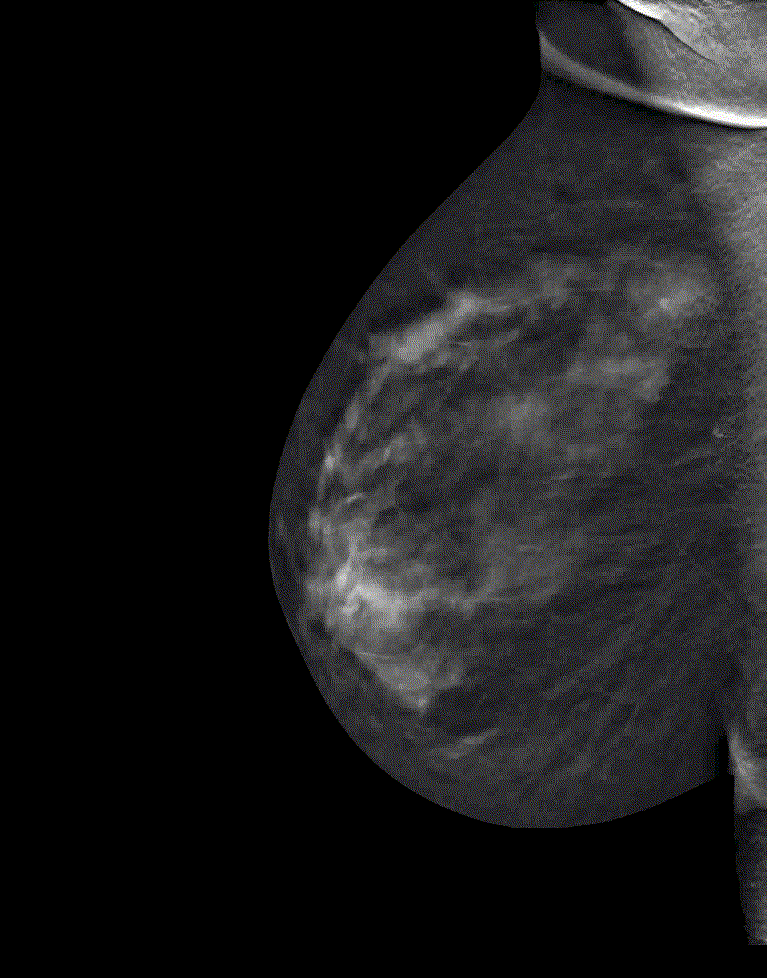

Mammography is an effective tool in detecting suspicious breast lesions. However, like any method, it is not perfect. In mammography, we obtain 2D images that show superimposed tissues. Many times, this causes problems in differentiating truly suspicious densities from apparent lesions resulting from superimposition of glandular tissue from several sites. This case report aims to demonstrate the usefulness of digital tomosynthesis in differentiating densities of unclear nature.